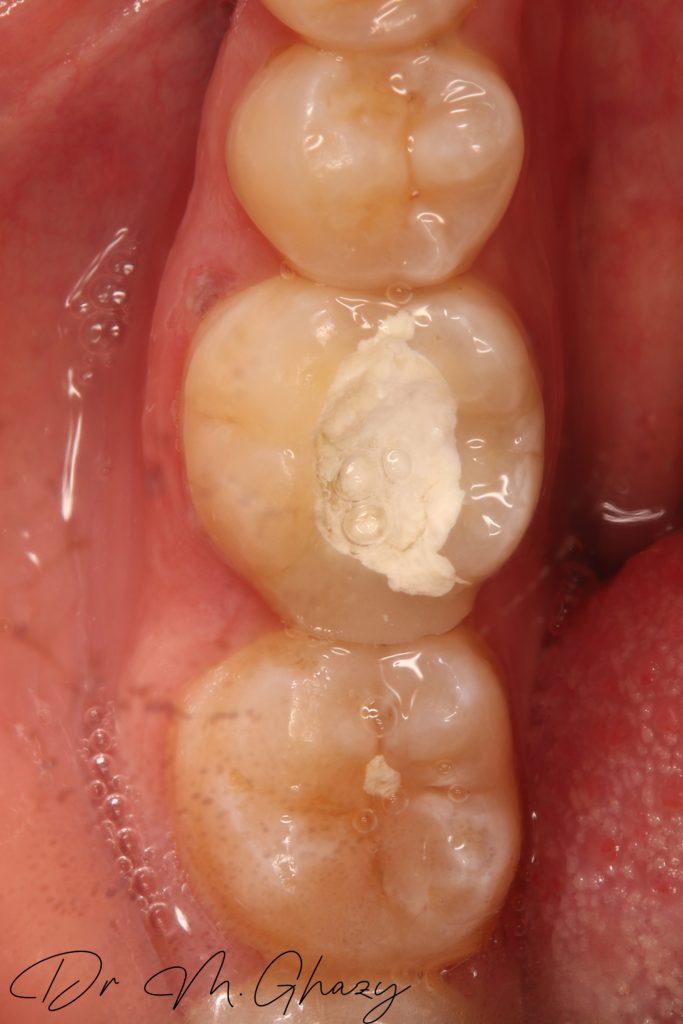

Occlusal clearance

Final impression